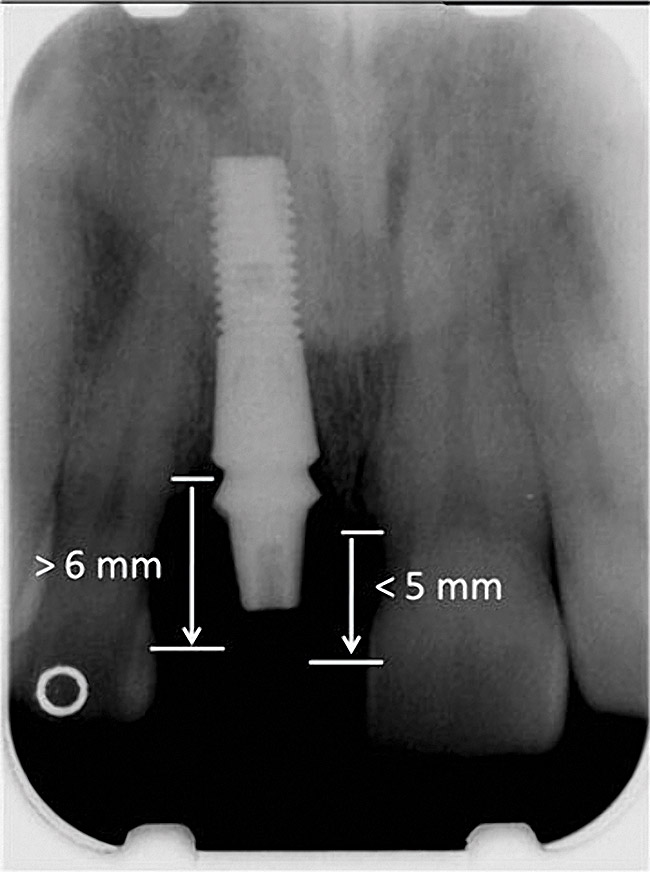

Figure 2 Identification of sufficient inter-radicular space: The radiographic representation of inter-radicular space (Fig 2) reveals abundant space for a single-tooth implant; at the alveolar crest,

> 6 mm of interproximal space is available for placeme

Figure 2

Figure 3 Identification of sufficient inter-radicular space: The radiographic representation of inter-radicular space (Fig 2) reveals abundant space for a single-tooth implant; at the alveolar crest,

Figure 3

Figure 4 Characterization of the interproximal bone and tooth contacts: A periapical radiograph assists in measuring the distance from bone crest to the adjacent tooth contact points for missing tooth No. 8. The mesial bone crest to the adjacent tooth con

Figure 4

Figure 5 Characterization of the interproximal bone and tooth contacts: A periapical radiograph assists in measuring the distance from bone crest to the adjacent tooth contact points for missing tooth No. 8. The mesial bone crest to the adjacent tooth con

Figure 5

The typical minimal mesiodistal dimension that may be considered for simple single-tooth replacement of an anterior tooth is 6 mm. This may not seem to be an impediment to implant placement; however, several common anatomic situations are often encountered. While the typical dimension of a lateral incisor is greater than 6 mm in the mesiodistal dimension, teeth are often lost without immediate placement, and the bound edentulous space may be reduced. Natural tooth crowding with rotation may result in less than 6 mm of mesiodistal dimension. Another concern is proximal root convergence leading to less than 6 mm of space for implant placement despite the dimension available for the crown. Finally, lateral incisor agenesis that is treated by orthodontics may not always provide 6 mm of space for implant placement or may result in proximal root convergence. There must exist 6 mm of mesiodistal bone dimension between adjacent teeth to permit an implant (> 3.5 mm in diameter) to be placed with greater than 1 mm of bone at mesial and distal interproximal locations (Figure 2 and Figure 3). The advent of narrow implants (eg, 3 mm) provides a new opportunity to address smaller (approximately 5 mm) mesiodistal dimensions.

Additional attention must be paid to the osseous architecture related to the adjacent teeth, as this controls interproximal tissue form.7 The crest of healthy bone is 4.5 mm to 5 mm from the contact point between anterior teeth8; a similar 5-mm distance from the contact point to the bone crest has been measured between an implant and natural tooth. An important and additional rule to guide esthetic implant outcomes is that the adjacent tooth should possess interproximal bone levels no further than 6 mm from the natural tooth contact point (Figure 4 through Figure 6). While the ideal distance is justifiably indicated to be 5 mm, this 6-mm rule establishes a point at which marked interproximal tissue deficiencies and asymmetry will not be overcome.